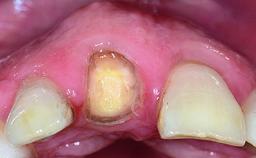

A healthy 37-year-old female patient was referred for a consultation on the replacement of missing tooth 21 with an implant-supported restoration. She stated that several years previously the tooth had been traumatically avulsed following a motor vehicle accident. The tooth was replaced with a three-unit fixed partial denture (FPD) immediately afterwards. Over time, she became disillusioned with the FPD and looked for a different option, including orthodontic therapy. She presented still in her orthodontic appliances, with the pontic sectioned free from the FPD but attached to the archwire. Her orthodontist felt that orthodontic treatment had been successfully completed, but nevertheless referred her before removing the appliances in case adjustments were necessary.

Abutment Type CAD/CAM

Prosthesis Type FDP

Retention Cemented, with prosthesis margin < 3mm submucosal Cemented, with prosthesis margin < 3mm submucosal